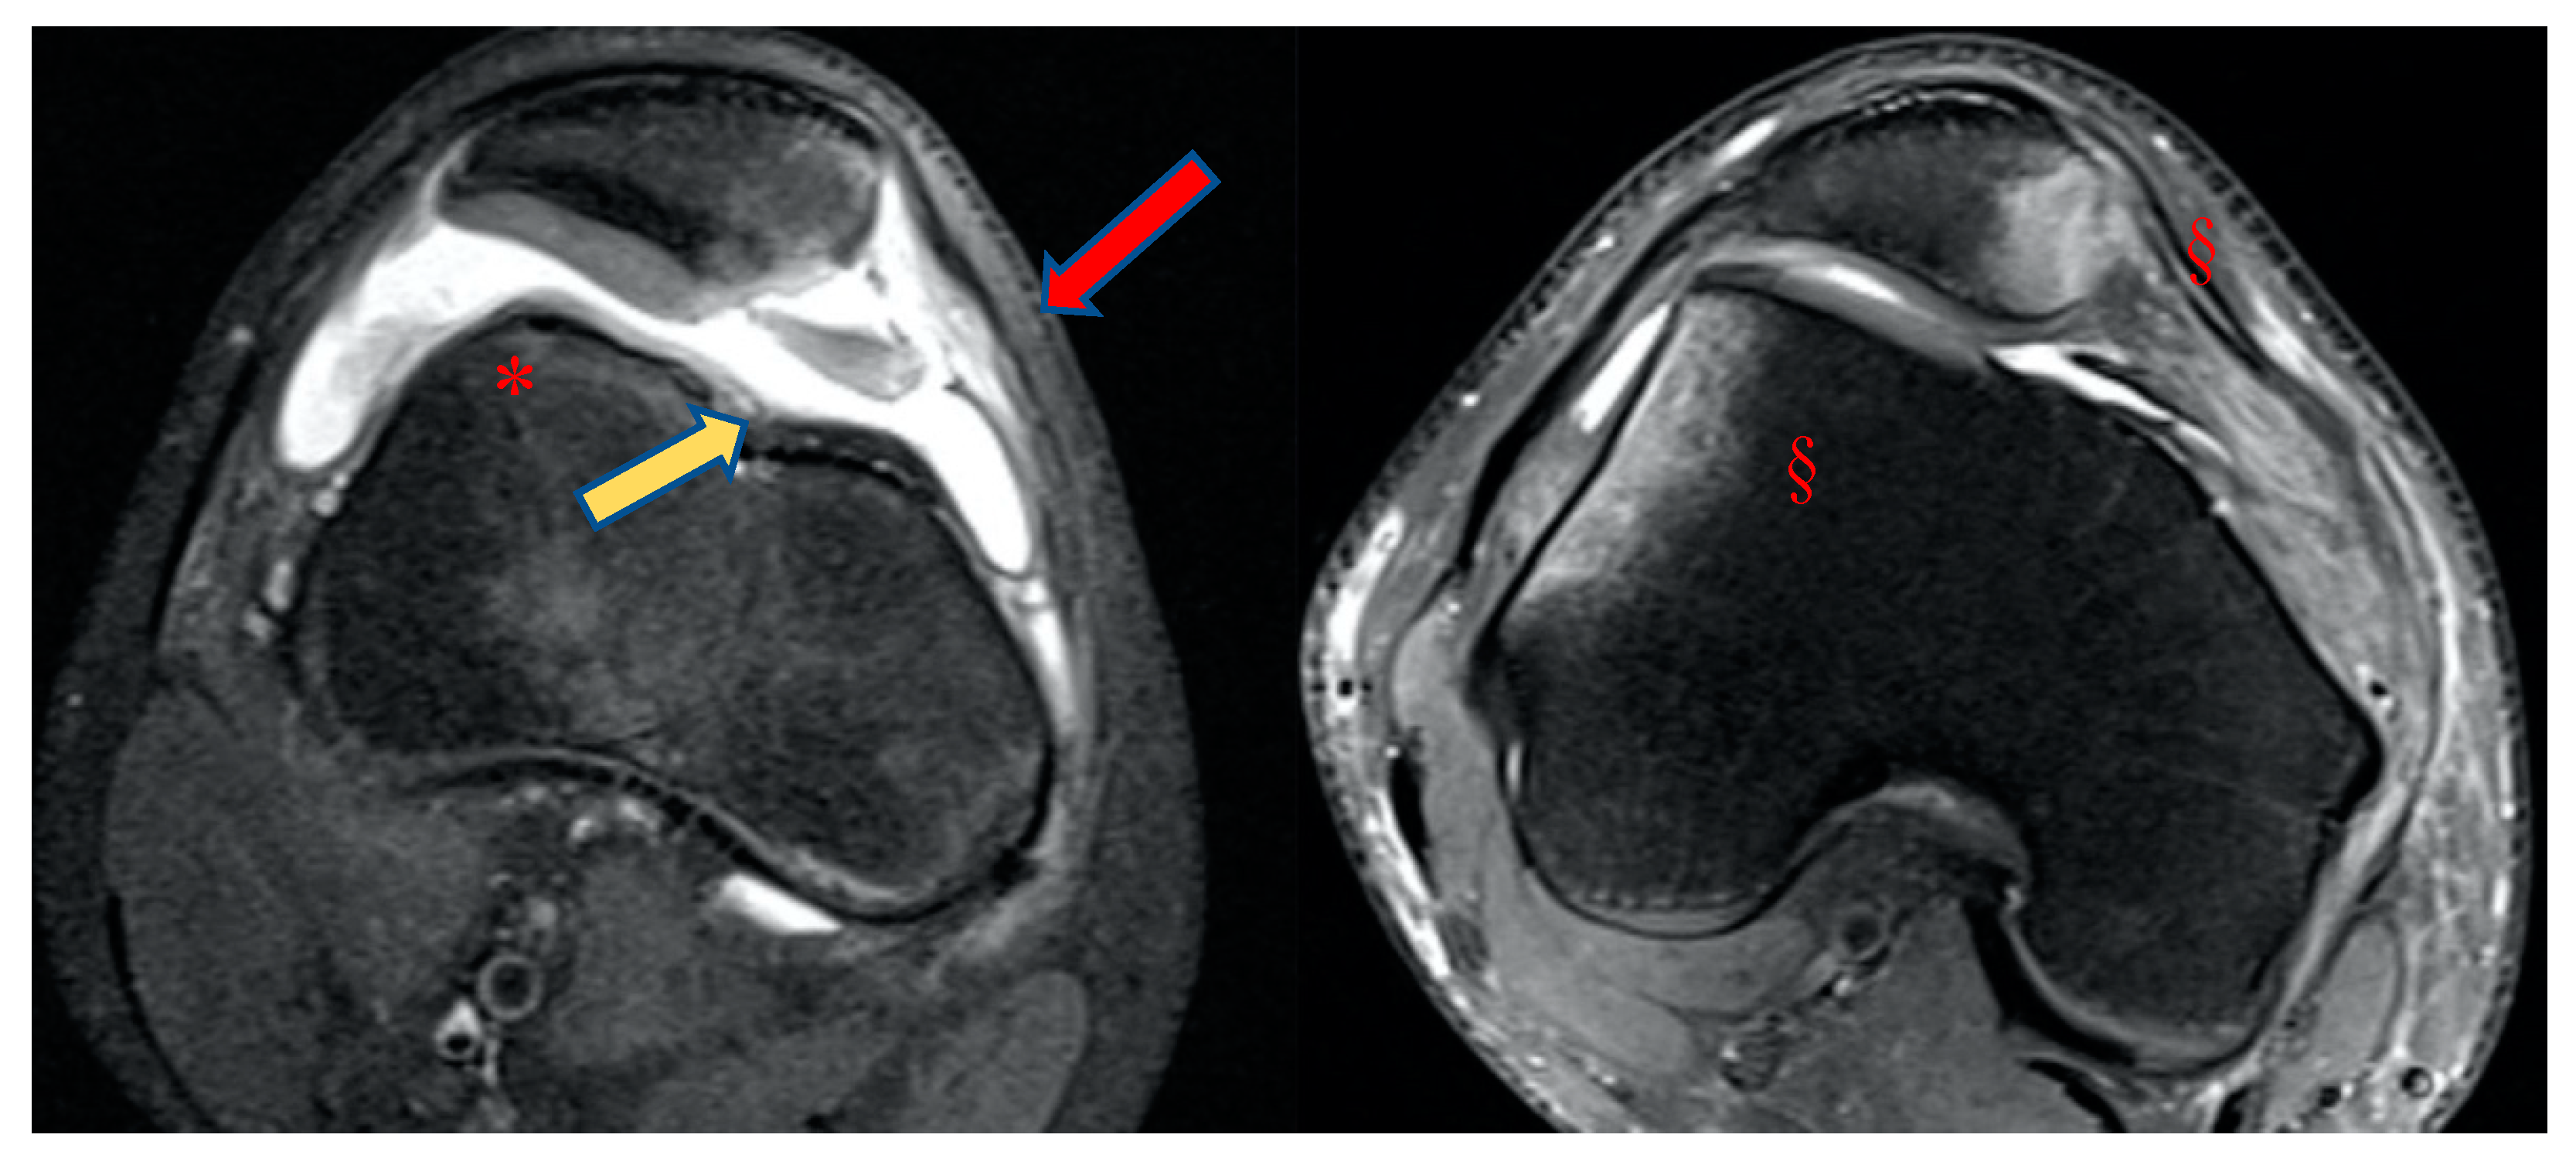

Figure 2. Types trochlear dysplasia on MRI axial view, classified by Dejour [7].

Figure 7. Case of primary patellar dislocation, MRI axial views. Note: a large amount of synovial fluid or hemarthrosis (*), the bone bruise on its typical presentation (§), the chondral defect on the medial side of the patella (red arrow), and the shape of the trochlea (yellow arrow).